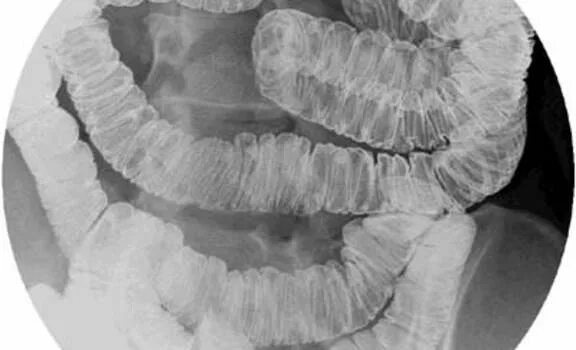

Пассаж кишечника